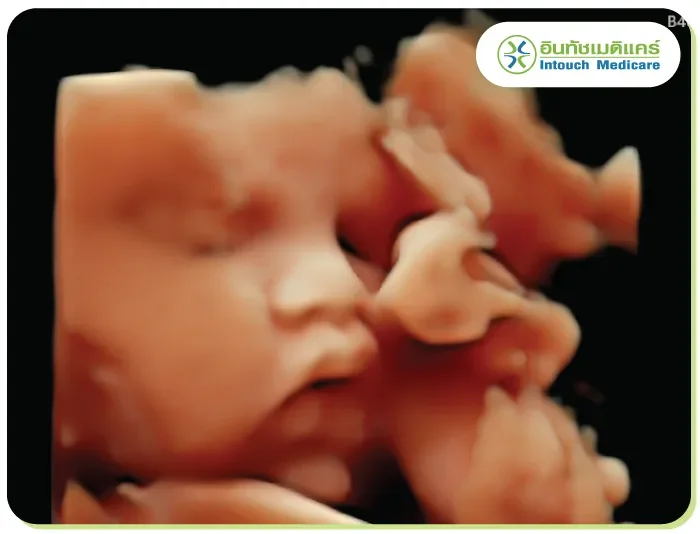

จะแสดงภาพให้เห็นทั้งความกว้าง ความสูง และความลึก โดยการรับสัญญาณคลื่นเสียงที่สะท้อนออกมา ผ่านการวิเคราะห์ด้วยโปรแกรมคอมพิวเตอร์ จึงได้ภาพที่มีรายละเอียดชัดเจน เสมือนจริงกว่าแบบ 2 มิติ

จะคล้ายกับแบบ 3 มิติ แต่จะมีการประมวลผลที่ซับซ้อนขึ้น โดยการนำภาพแบบ 3 มิติมาแสดงผลเรียงต่อกันจนเกิดเป็นภาพเคลื่อนไหวเสมือนจริงแบบ Real- time เห็นรายละเอียดได้อย่างชัดเจน นิยมนำมาใช้ในทางการแพทย์มากขึ้น

อัลตร้าซาวด์ท้องหรือการตรวจครรภ์ (Obstretics) ตรวจเพื่อคำนวณวันคลอด ภาวะการตั้งครรภ์แฝด การตั้งครรภ์นอกมดลูก ตรวจความแข็งแรง ตรวจหาความพิการแต่กำเนิดของทารก ในสมอง ไขสันหลังหัวใจหรือส่วนอื่นๆ ของร่างกาย ของทารกในครรภ์ ตรวจปริมาณน้ำคร่ำ ตำแหน่งของรก รวมทั้งสามารถดูเพศและประเมินน้ำหนักของเด็กได้อีกด้วย

บอกอายุครรภ์ได้ รู้การเคลื่อนไหวและอัตราการเต้นของหัวใจของทารก การตรวจแบบ 4 มิติ จะช่วยตอบโจทย์มากกว่า ซึ่งสถานพยาบาลเอกชนจะมีบริการแบบ 4 มิติ ราคาสบายกระเป๋าให้คุณแม่เลือกใช้บริการตามที่ต้องการได้

จะเห็นได้ว่าการอัลตร้าซาวด์นั้น มีความจำเป็นในทางการแพทย์เป็นอย่างมาก ทั้งกับการตรวจเพื่อคัดกรองโรคต่างๆ รวมทั้งช่วยให้คุณแม่ได้เห็นใบหน้าและการเคลื่อนไหวของเจ้าตัวเล็กตั้งแต่อยู่ในครรภ์